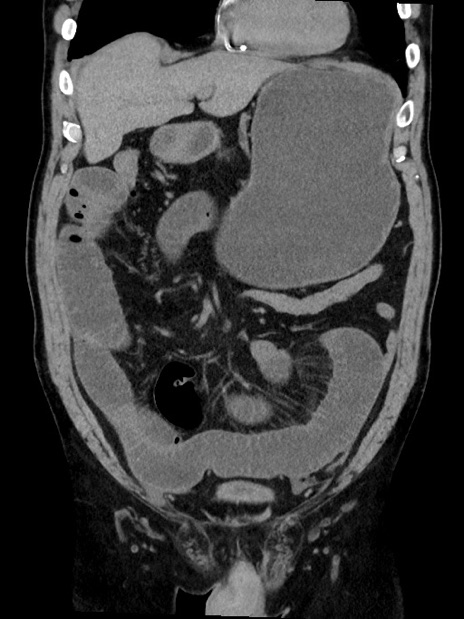

症例35(冠状断像)

【症例】70歳代 男性

【主訴】腹部膨満、嘔吐

【現病歴】昨日より腹部膨満感出現。本日増悪し、仙痛出現。嘔吐あり、受診。

【既往歴】糖尿病、胆摘後

【身体所見】BP 149/80mmHg、HR 74/min、BT 35.9℃、腹部:膨満、軟、圧痛なし。腸雑音減弱あり。上腹部正中切開瘢痕あり。

【データ】WBC 13500、CRP 1.72